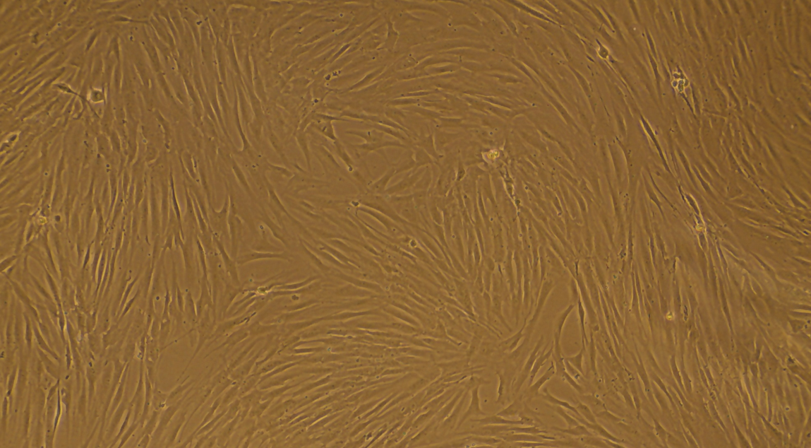

Primary cells offer a truly authentic glimpse into human biology, capturing the essence of naturalcell behaviour far more accurately than immortalised cell lines. By preserving their original shapeand function, these cells respond in culture much like they do within the body, providingresearchers with a window into genuine physiological processes. Whether modelling complexconditions or exploring new scientific questions, primary cells deliver the reliability and realism thatdrive meaningful discoveries. Designed for ease and consistent results, they form the essentialgroundwork for research that truly reflects life as it is.